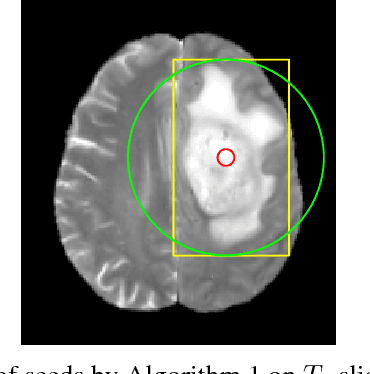

Abstract:Inspired by the success of Convolutional Neural Networks (CNN), we develop a novel Computer Aided Detection (CADe) system using CNN for Glioblastoma Multiforme (GBM) detection and segmentation from multi channel MRI data. A two-stage approach first identifies the presence of GBM. This is followed by a GBM localization in each "abnormal" MR slice. As part of the CADe system, two CNN architectures viz. Classification CNN (C-CNN) and Detection CNN (D-CNN) are employed. The CADe system considers MRI data consisting of four sequences ($T_1$, $T_{1c},$ $T_2$, and $T_{2FLAIR}$) as input, and automatically generates the bounding boxes encompassing the tumor regions in each slice which is deemed abnormal. Experimental results demonstrate that the proposed CADe system, when used as a preliminary step before segmentation, can allow improved delineation of tumor region while reducing false positives arising in normal areas of the brain. The GrowCut method, employed for tumor segmentation, typically requires a foreground and background seed region for initialization. Here the algorithm is initialized with seeds automatically generated from the output of the proposed CADe system, thereby resulting in improved performance as compared to that using random seeds.